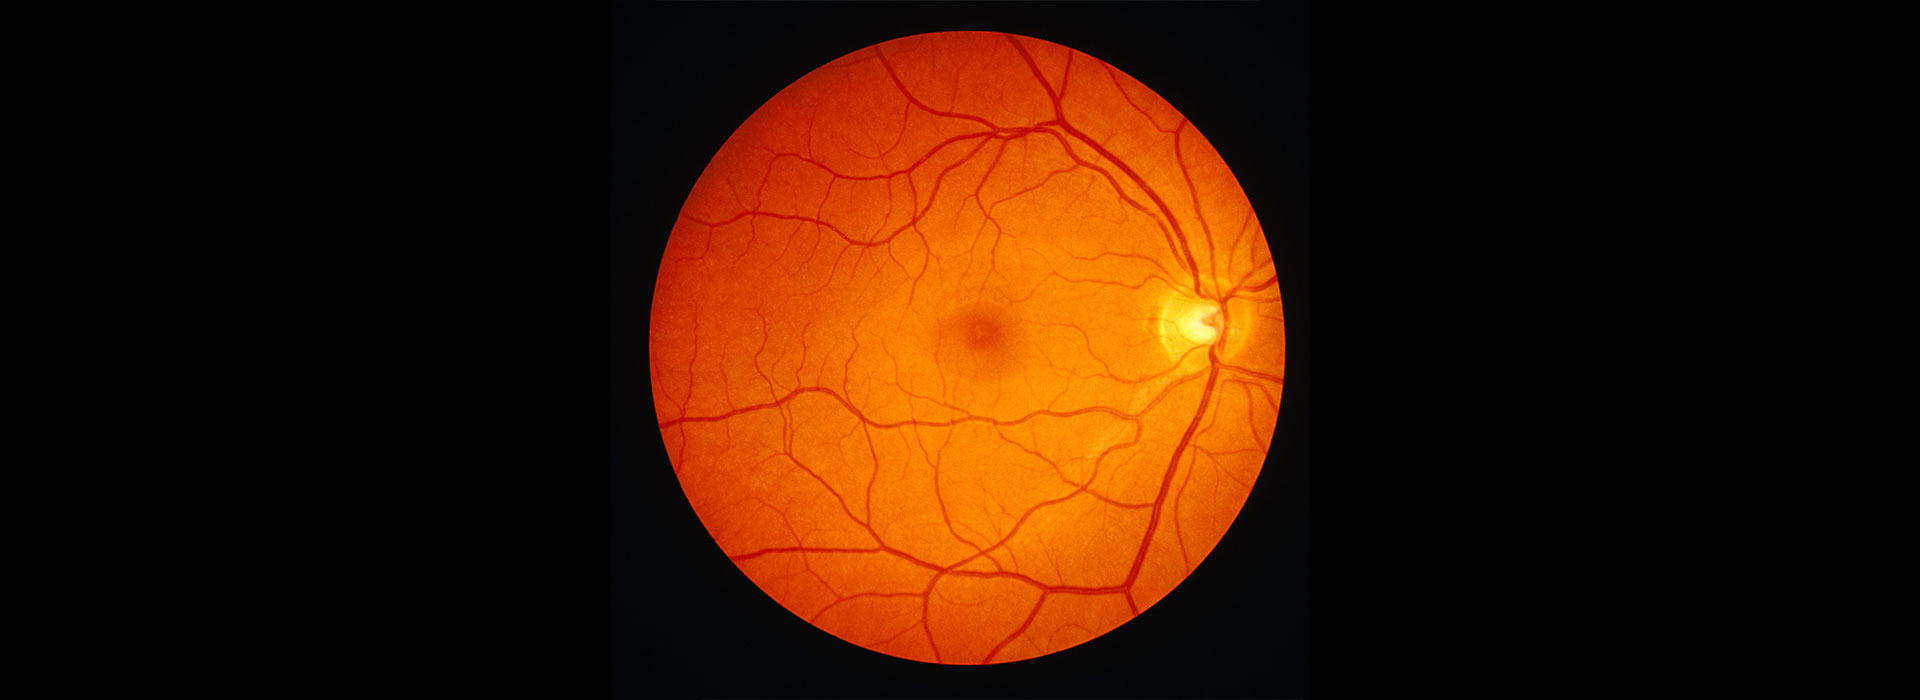

Атрофия зрительного нерва Лебера: Симптомы и лечение